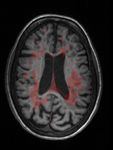

Individuazione lesioni cerebrali da immagini di risonanza magnetica Individuare lesioni da Sclerosi Multipla in immagini di risonanza magnetica: LESIONI MASCHERA Ing. Corinna Vitale 23/06/2021 9

Individuazione lesioni cerebrali da immagini di risonanza magnetica Individuare lesioni da Sclerosi Multipla in immagini di risonanza magnetica: Classificazione & Segmentazione LESIONE = 0 1. Nell’immagine ci sono lesioni? 2. Quali sono i pixel lesionati? INPUT LESIONE = 1 OUTPUT Ing. Corinna Vitale 23/06/2021 10

Costruzione del dataset CARICO LESIONALE BASSO MEDIO ALTO Tre pazienti con diverso carico lesionale Corinna Vitale 23/06/2021 16